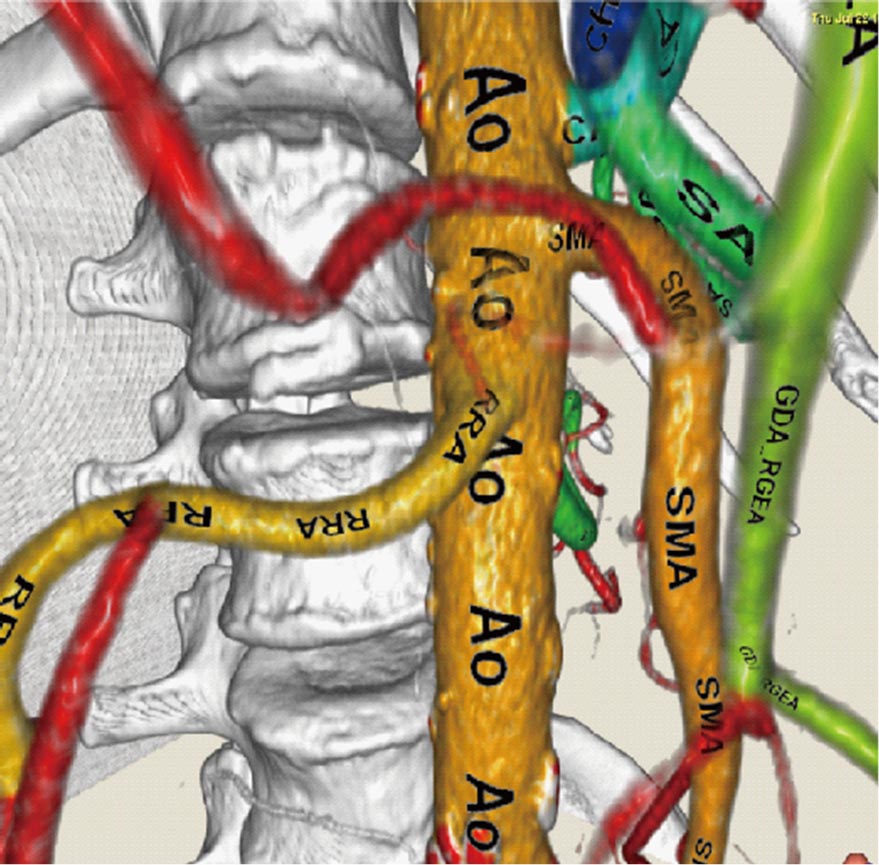

患者さんの解剖学的な構造は一人ひとり異なるため、手術前に撮影されるCT像を用いて、各患者さんの臓器位置、形状、血管分岐パターンなどを解析します。そして、この解析結果を、コンピュータグラフィックスの技術により3次元的に可視化します。CT像から臓器が存在する領域を取り出す処理はセグメンテーション処理と呼ばれています。最近では、大規模な医用画像データベースとそれに付与されたラベル画像から、未知画像に対して精度よく臓器領域を抽出手法が実現されています。さらに、血管などには解剖学的名称が自動的に対応付けられます。このような結果を基にして、個々の患者さんの3次元画像を構築し、手術シミュレーション画像として利用します。また、臓器変形などをシミュレーションすることもできます。

図2 CT像からの腹部臓器セグメンテーションの例

図3 腹部動脈の血管名表示結果